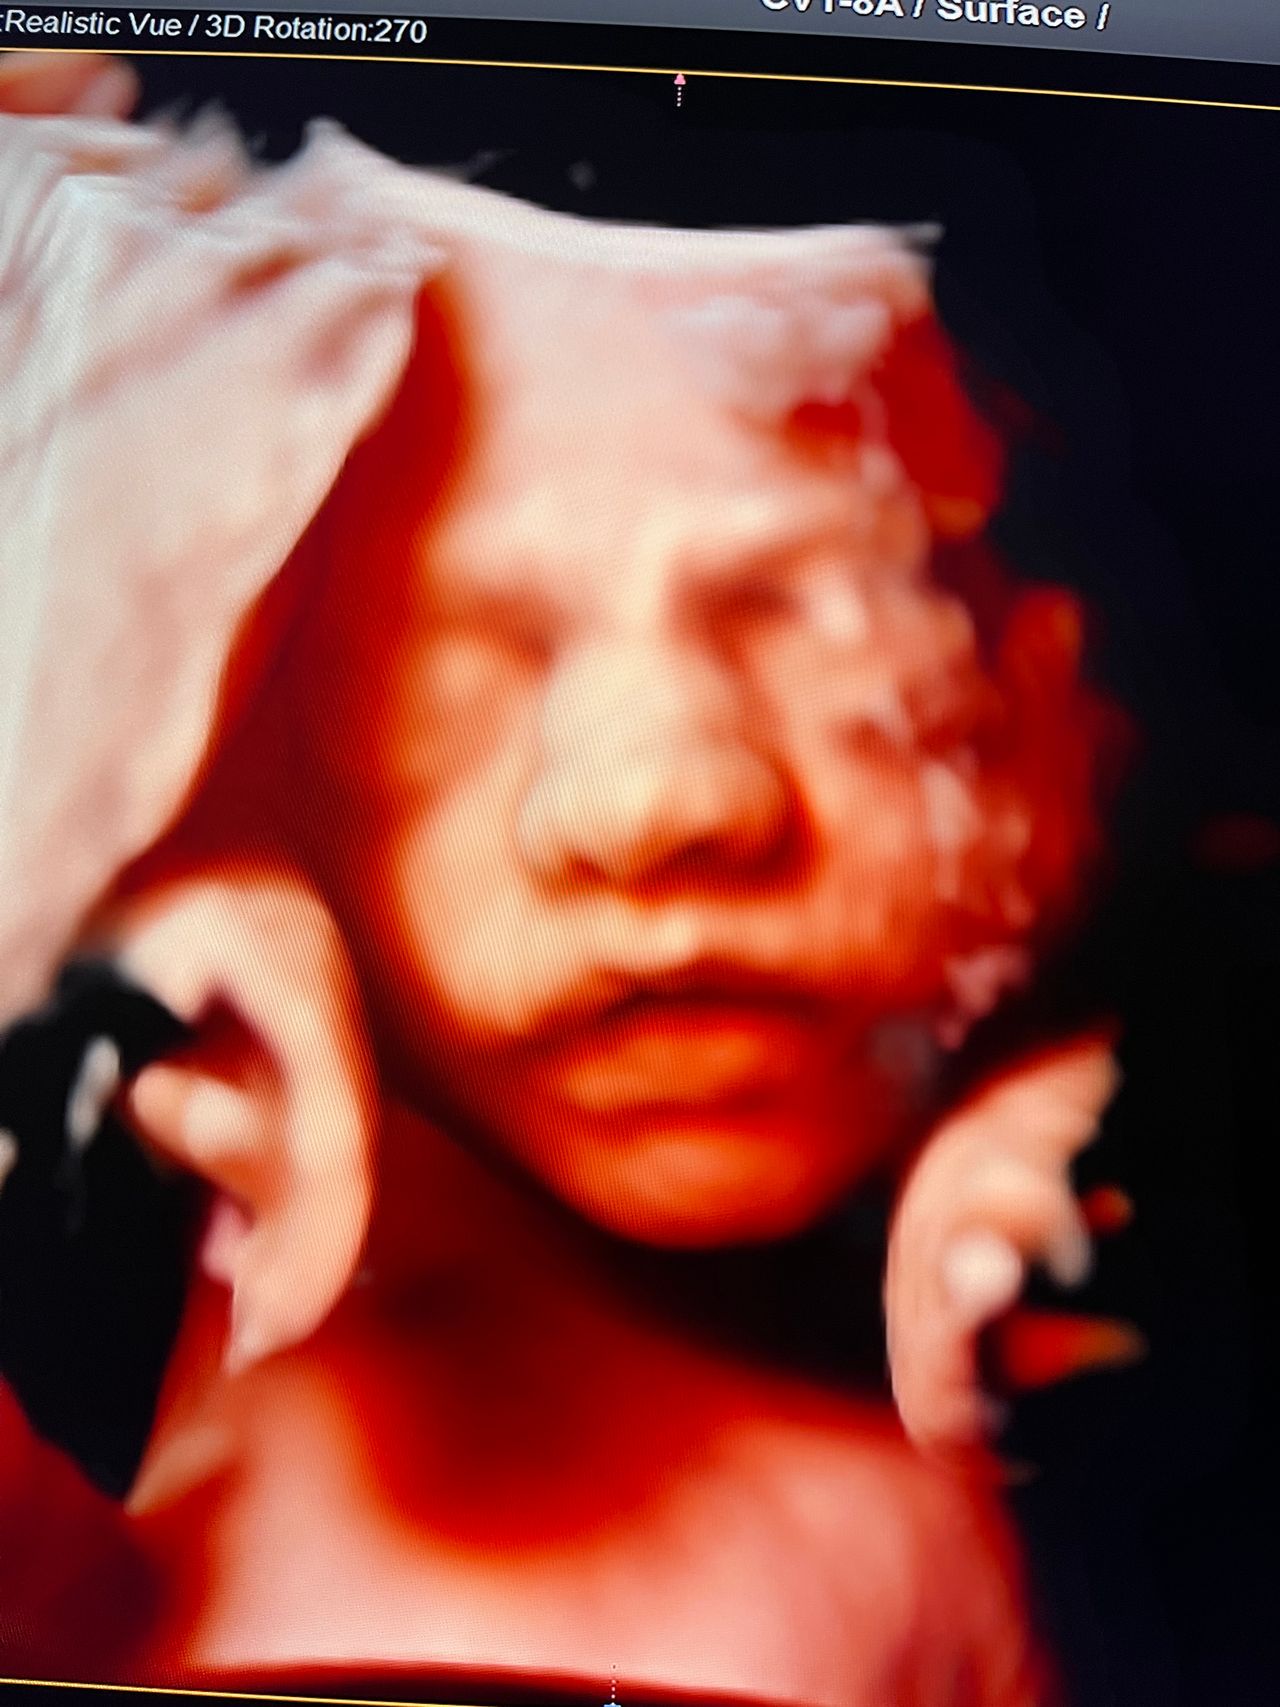

Attualmente lavoro come Dirigente medico nella SC di Ostetricia e Ginecologia dell'Ospedale Michele e Pietro Ferrero di Verduno, mi occupo prevalentemente di screening prenatale, ecografia ostetrica del I trimestre( misurazione translucenza nucale,NT), ecografia morfologica del II trimestre, ambulatorio pregresso taglio cesareo, ecografia ostetrica 3D. Seguo le gravidanze fisiologiche e quelle ad alto rischio , presto servizio in sala parto. Eseguo visite ginecologiche di I-II livello in regime ambulatoriale, counseling contraccettivo ed eventuale prescrizione pillola, inserimento spirale (IUD), dispositivo sottocutaneo (Nexplanon).

Foto e video